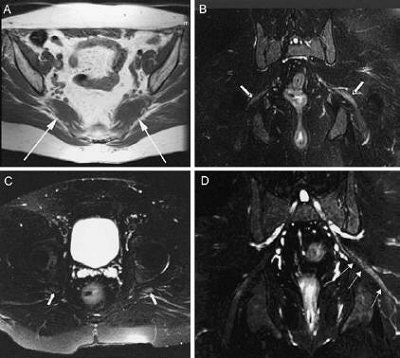

| Magnetic resonance neurography findings in piriformis syndrome. A: Axial T1-weighted image of piriformis muscle size asymmetry (arrows indicate piriformis muscles). The left muscle is enlarged. B and C: Coronal and axial images of the pelvis (arrows indicate sciatic nerves). The left nerve exhibited hyperintensity. D: Curved reformatted neurography image demonstrating left sciatic nerve hyperintensity and loss of fascicular detail at the sciatic notch (arrows). Filler AG, Haynes J, Jordan SE, et al, "Sciatica of nondisc origin and piriformis syndrome: Diagnosis by magnetic resonance neurography and interventional magnetic resonance imaging with outcome study of resulting treatment," J Neurosurg Spine 2: 99-115, 2005, Figure 5. |

Successful MR neurography was based on two findings: piriformis muscle asymmetry and unilateral sciatic nerve hyperintensity at the level of the sciatic notch. Together, these criteria gave MR neurography a high specificity of 93% and a moderate sensitivity of 64%.